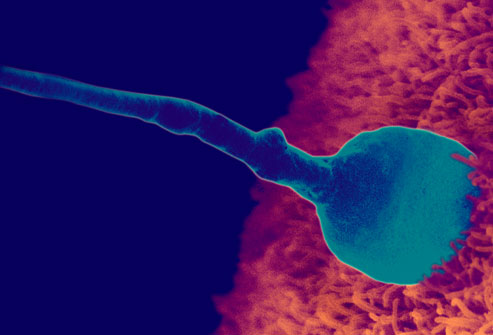

Коли сперматозоїд зустрічається з яйцеклітиною, він її запліднює. Цей процес називається зачаття. У цей момент завершується організація генетичного матеріалу, включаючи стать дитини. Протягом трьох днів після зачаття, запліднена яйцеклітина (яка з цього моменту починає швидко ділитися на безліч клітин) проходить через фаллопієві (маткові) труби в матку, де кріпиться до маткової стінки. В цей же момент починає формуватися плацента, яка буде живити малюка.